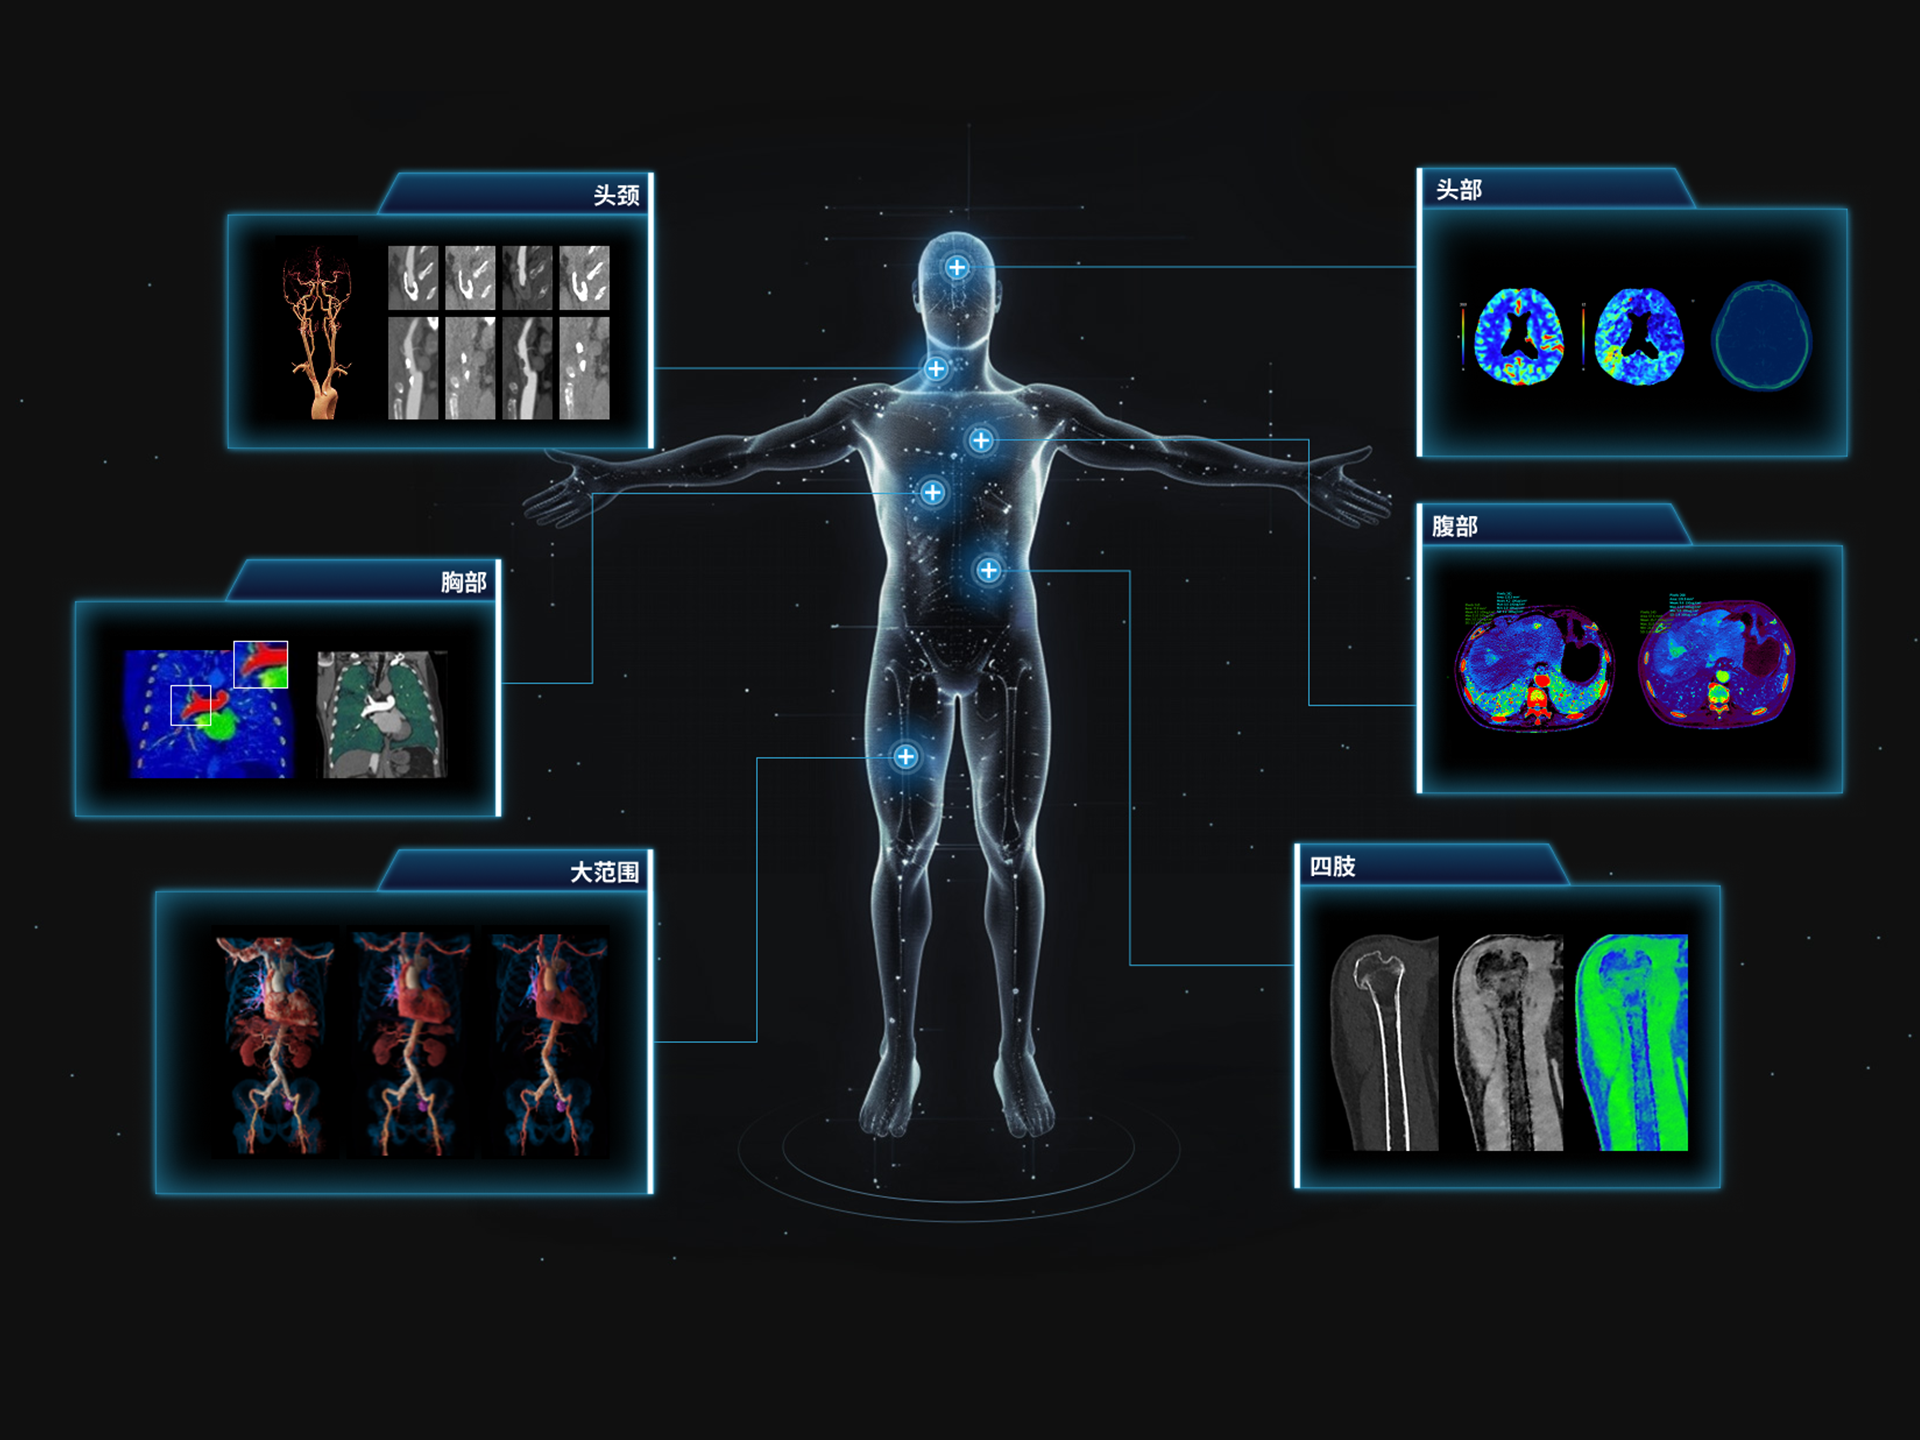

全身高清能谱成像

470 mm

• 双宽大视野

• 支持全身各部位能谱成像

• 支持全身各部位、各类能谱成像

uCT SiriuX® 依托16cm超宽探测器与双源能谱技术,实现真正意义上的全身高清能谱成像。单次扫描同步获取灌注、能谱等多维定量参数,精准解析组织特性与病灶成分,为临床决策提供更深层次的诊断依据。